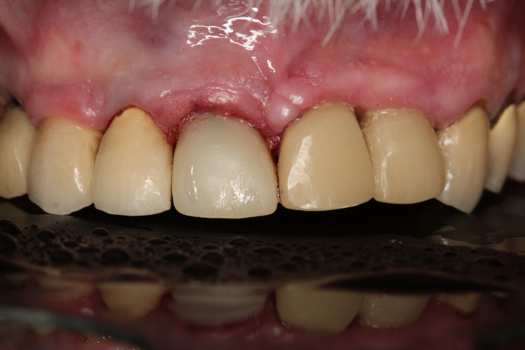

Fig 6. Image of the patient’s mature smile.

Figure 6

Figure 6 and Figure 7 depict a mature smile with many implant restorations. An analog impression was sent to the laboratory. The impression was scanned by the laboratory, a model was created virtually, and the implant dimensions and position were defined. The 3D surgical guide was fabricated (Figure 8), allowing the patient to receive his therapy swiftly and predictably. Tooth No. 8 was extracted, and the implant was placed and immediately loaded with an acrylic provisional treatment crown (Figure 9). The screw-retained treatment crown was fabricated in-office from a previously completed diagnostic wax-up.